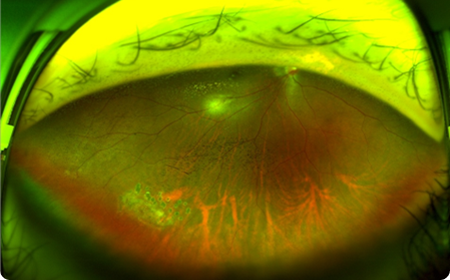

OPTOS–Daytona

무산동 광각 안저 촬영기

무산동 상태에서 전체 망막의 200도

(약 80%)범위의 촬영이 가능해 망막의 중심부와 주변부를 빠르게 확인할 수 있습니다.

평소에 인지 하지 못하던 망막주변부의 질환

(망막열공,변성 등)에 대한 조기 진단이 가능합니다.

무산동 검사 장비이기 때문에 산동

(동공확장)하기 위한 대기시간이 없으며,

검사 후에도 불편함없이 일상생활이 가능합니다.